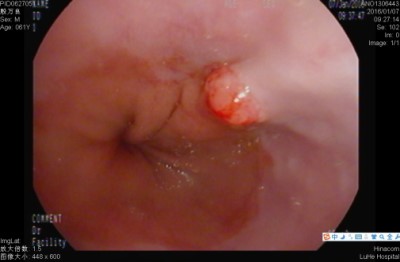

一、食管贲门癌

食管癌的早期信号:(1)噎食:就是咽食物时有阻力,咽食不畅,有堵塞感、或有异物感,呈渐进性加重,(2)吞咽困难:吞咽时胸骨后有轻度闷、胀不适感或隐痛感,常在饮水、喝酒或喝酸性饮料时,出现食管内持续性灼痛或刺痛。(3)吞咽异物感:吞咽时自觉食管内有异物,似饭粒或茶叶碎片黏附于食管上,咽之不下,吐之不出。以上三种症状的发生率占全部早期食管癌症状的80%以上,而吞咽不适的感觉占全部症状的30%以上。